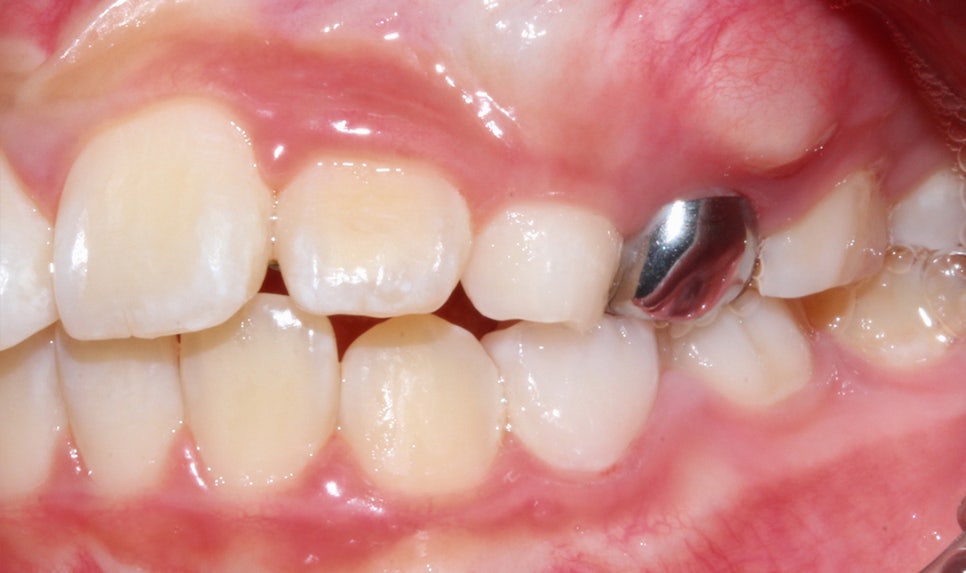

Before / after

상하악 Clippy-C (클리피씨) 전체 교정

구치부 반대교합은 통상적으로 비발치 교정일 경우에는

1년~1년 반 정도 교정 기간을 생각하고 있었어요-:D

2년이라는 기간이 걸린 이유는

교정 마지막 단계인 고무줄을 자주 안 걸어

주는 바람에 교정 기간이 많이 늘어났네요...!

어린이 치아교정 후 모습

2D 치과(투디 치과)